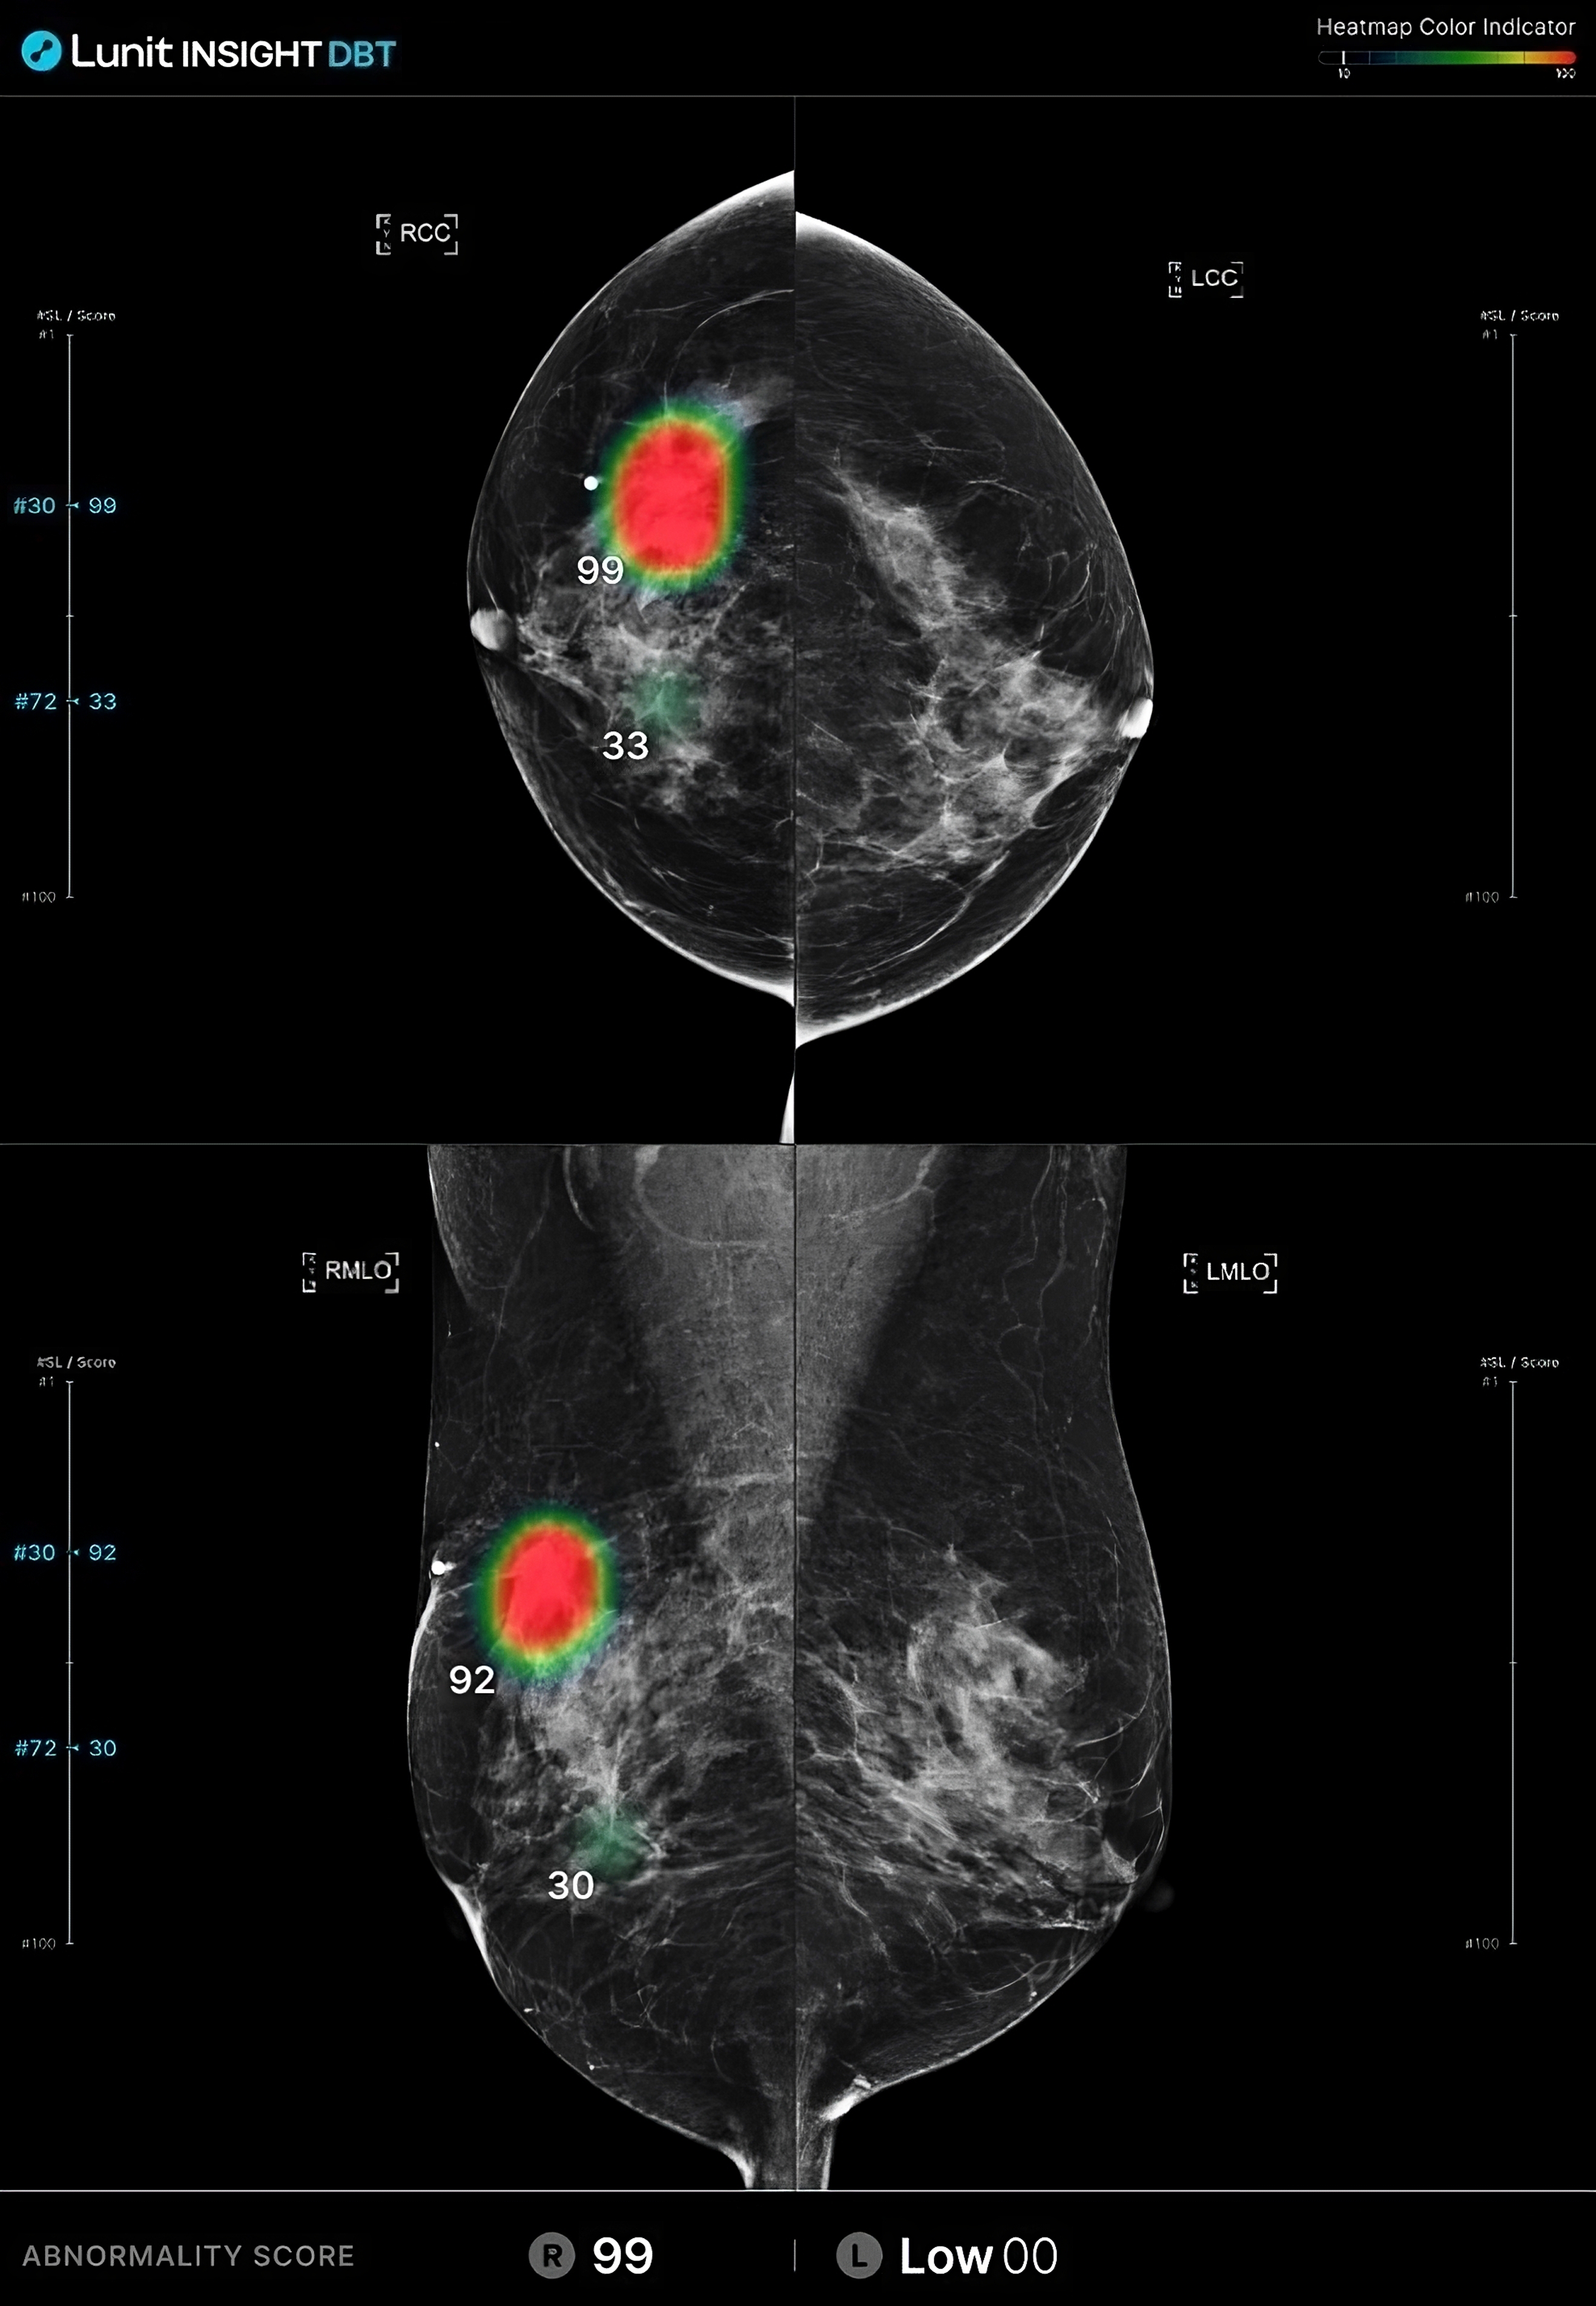

루닛 인사이트 DBT는 3D Tomosynthesis 영상을 분석하여 유방암 의심 부위를 검출합니다.

유방암 의심 부위의 존재 가능성을 0-100의 숫자로 나타냅니다. 숫자가 높을수록 악성 병변의 존재 가능성이 높습니다.

병변 유형 표시:

결과영상 화면 종류:

결과영상 화면에서 병변이 검출된 슬라이스의 번호와 점수를 확인(SC)할 수 있고, 클릭 시 해당 슬라이스로 바로 이동(CAD SR) 할 수 있습니다.